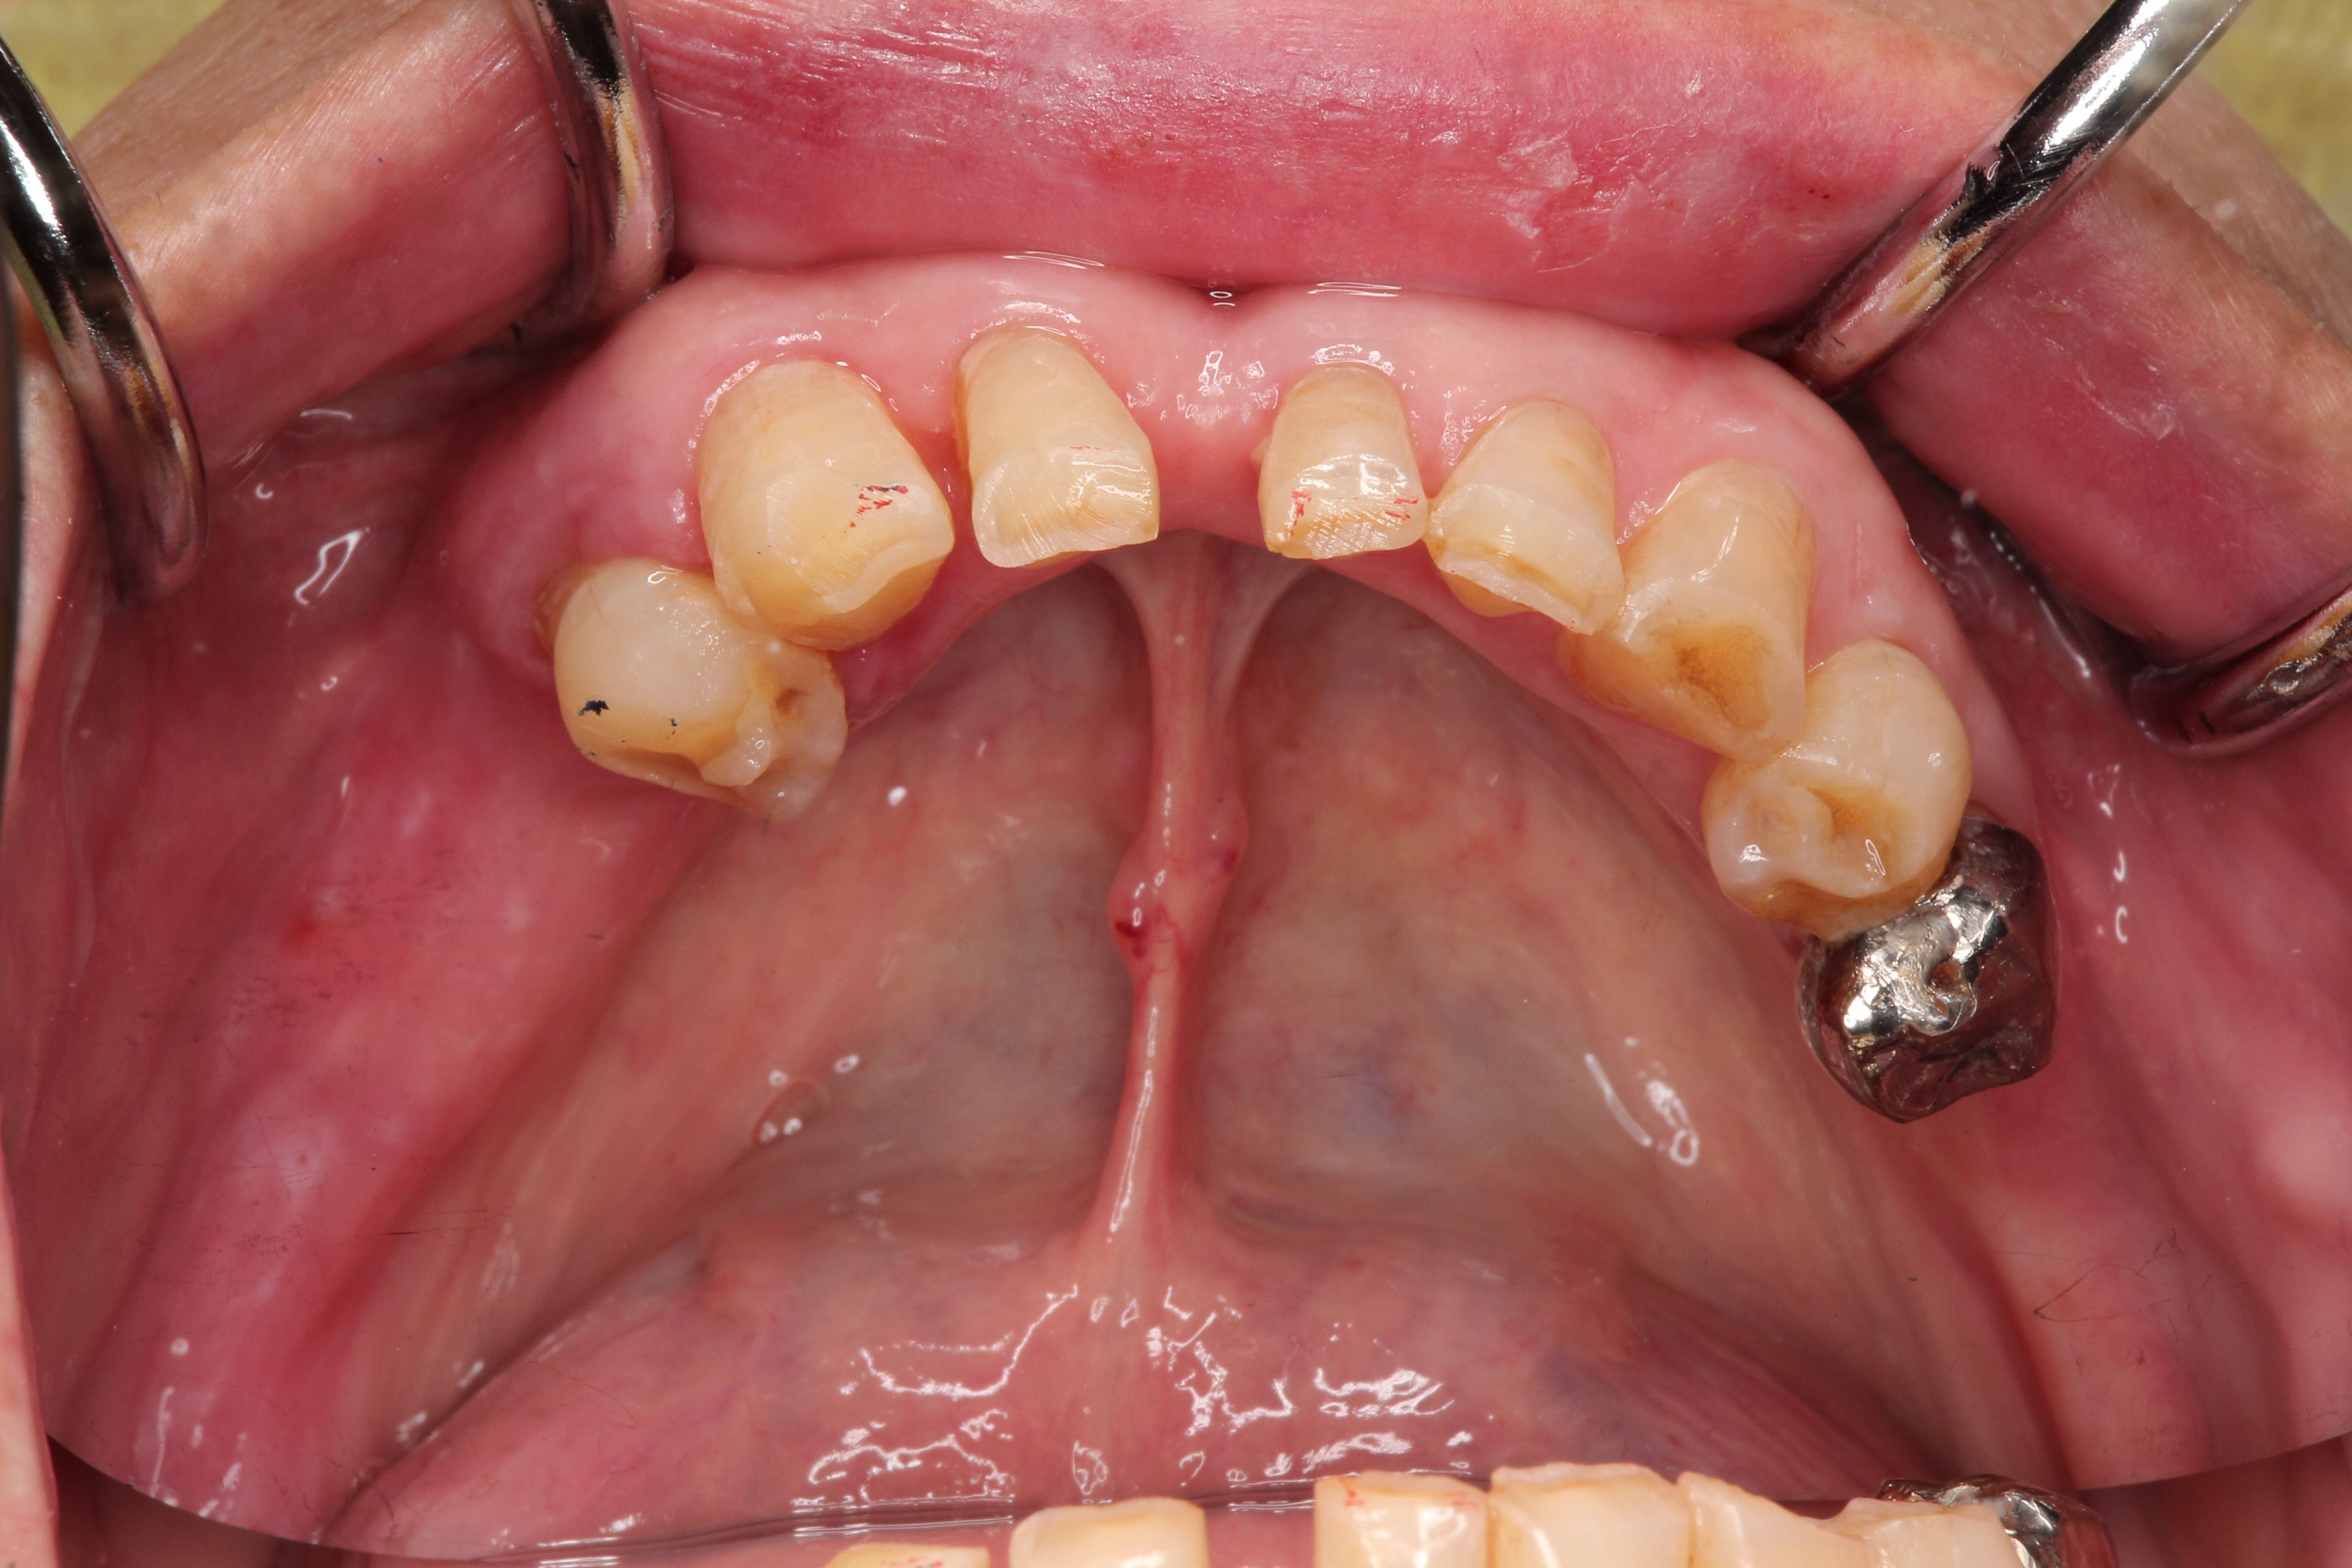

こちらも正中をまたいでいますが残存歯の後方部が両方ともないのでKennedy I級です。

こちらは歯と歯に囲まれた欠損(中間欠損)となりますのでKennedy Ⅲ級となります。